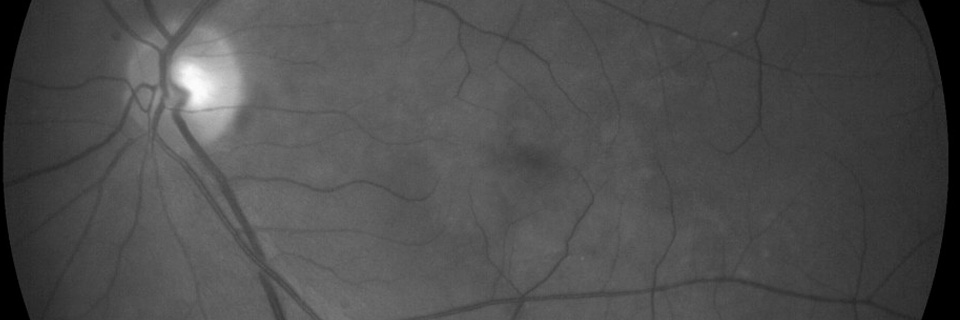

The three leading causes of blindness are diabetic retinopathy, glaucoma and age related macular degeneration in the US.

There are now treatments for age related macular degeneration that can return the patient to driving vision.